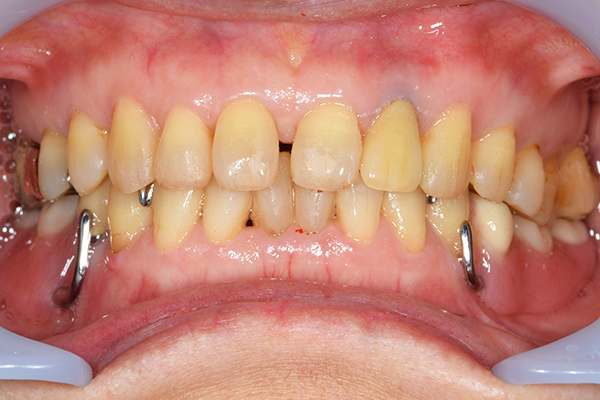

ケース4

(アタッチメントを用いた部分入れ歯)

右上のインプラント周囲炎で、その部分が痛いという患者様でした。 また奥歯で噛むことが難しかったため、前歯を使用することが多くなり、 前歯が前よりも前に出てきていることも気になっていらっしゃいました。

インプラント部以外にも歯周病が進行していましたので、歯周病の治療を行いました。 残念ながらインプラントと、1本の歯が残せなかったため抜歯を行いました。 その後、前歯の出っ張りを修正することと入れ歯の安定を図るため、残っている歯を全てかぶせ物にしていくことになりました。 写真中央は抜歯後に入れた治療用の入れ歯になります。 抜歯後歯ぐきが安定しましたら、入れ歯とかぶせ物の型取りを行いました。

噛み合わせチェックでしっかり奥歯で噛めるようにし、 歯を並べます。 その後、それに合わせて前歯を作っていきます。

最終的な入れ歯用の型取りをします。 シリコンで精密に型取りができました。

こちらが完成したかぶせ物と入れ歯です。かぶせ物にはアタッチメントをつけて金属のバネが見えない構造になっています。 入れ歯自体も金属を使用して、極力違和感がでないように、薄く作成しました。

お口の中に入れた状態です。 非常に見た目もよい出来となりました。 バネがみえないと見栄えが全然ちがいます。

年齢 70代・女性

主訴 奥歯のインプラントが痛い。

前歯がでてきた。

治療期間 6ヶ月

治療費 .メタルボンドクラウン7本:770,000円

.アタッチメント2個:220,000円

.義歯:550,000円

治療方針 ゆれてきたインプラントを抜去した後、歯周病の治療と、予後不良の歯を抜歯して、義歯を作成します。

抜歯後は治療用の入れ歯を作成し、ものが噛める様にします。

また前歯は、被せものをすることにしました。

治療内容 右上のボーンアンカードブリッジ(インプラントのブリッジ)部分がインプラント周囲炎になり、ぐらぐら揺れてきました。

そのため、インプラントを抜去した後、歯周病の治療と、予後不良の歯を抜歯して、義歯を作成していきました。

見た目が入れ歯とわからない様に針金のない、アタッチメントを使用した入れ歯を作成することにしました。

抜歯後は奥歯でものが噛める様に治療用の入れ歯を作成しました。

また前歯はフレアアウト(奥歯で噛めなくて前歯で噛む様になって、前歯が前に出てくる現象)していたため、患者さんの希望でかぶせ物をすることにしました。

特記事項 歯やインプラントを抜いた後は、2〜3ヶ月歯ぐきの回復を待ってから入れ歯を作るため、待機期間があります。その間、治療用の入れ歯を調整しながら使います。かぶせものをした後は歯がしみたり、場合によっては神経を抜く処置が必要になることもあります。